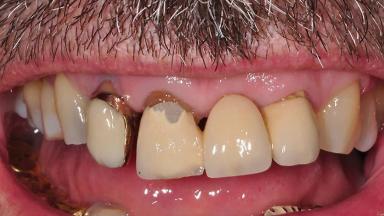

Surgical treatment of a 67-year-old male patient exhibiting an extended edentulous space in the anterior maxilla after the removal of three hopeless incisor teeth.